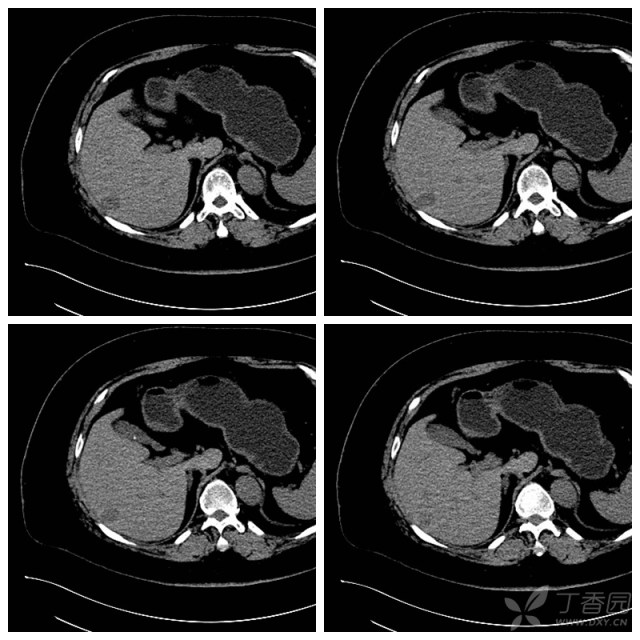

肝癌(原发性,肝叶外型)

老年男性 ,增强ct显示肝内多发大肝癌.

这是一个肝癌消融手术后复查的ct图像.

肝脏丨肝细胞肝癌